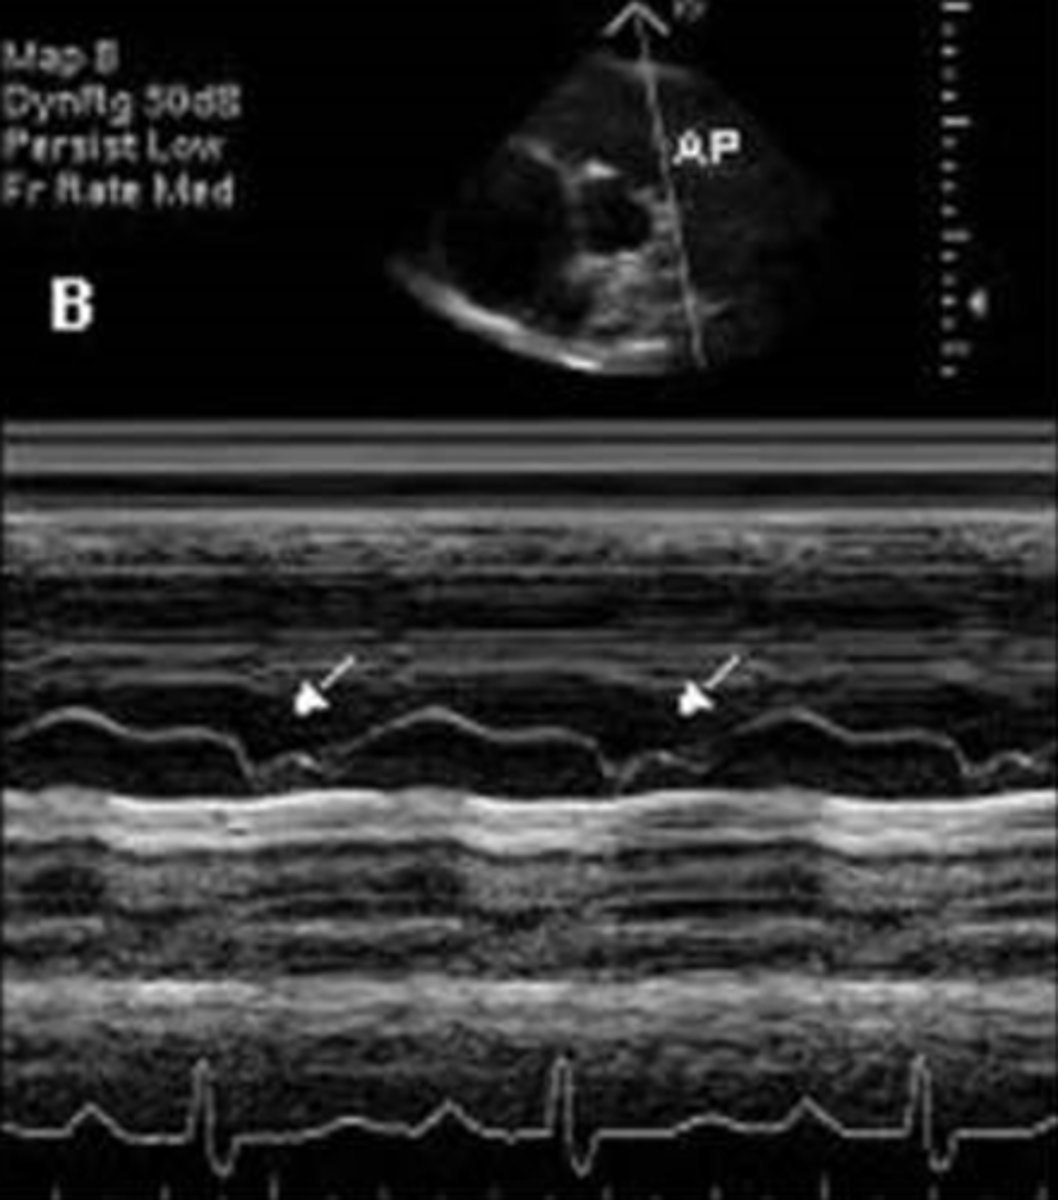

narrowing of the MV orifice with bright band of echoes in 2D and M-mode; thickening of AML and PML with anterior motion of PML; LA dilation and increased pressure; hockey puck appearance; decreased E-F slope and D-E excursion with diastolic doming

mitral valve stenosis